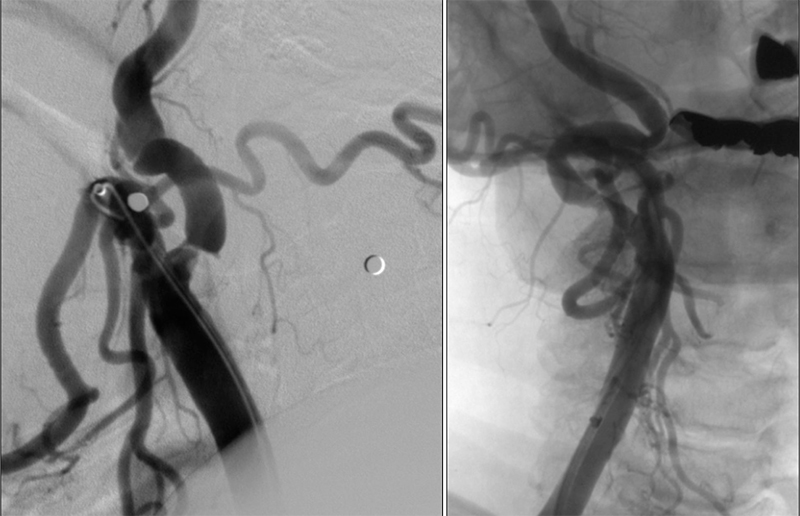

- Επιλέγουμε άπω προστασία (φίλτρα) σε:

- καλή ανατομία αορτικού τόξου

- χωρίς ενδοαυλικό θρόμβο ή μεγάλου βαθμού στένωση

- όταν η βλάβη εκτείνεται στην κοινή ή/και έξω καρωτίδα, ή υπάρχει απόφραξη της αντίστοιχης καρωτίδος (αντένδειξη γιά εγγύς προστασία)

- Επιλέγουμε εγγύς προστασία (σύστημα MOMA) σε:

- όταν υπάρχει ενδοαυλικός θρόμβος ή σοβαρή στένωση

- ελίκωση της μεταβολβικής έσω καρωτίδος, όταν δεν υπάρχει ζώνη προσγείωσης γιά το φίλτρο (landing zone)

- ιδιαίτερη προσοχή σε απόφραξη της αντίστοιχης καρωτίδος (μειωμένη ανοχή σε αποφρακτικό χρόνο)

- δεν μπορούμε να χρησιμοποιήσουμε ΜΟΜΑ όταν η βλάβη εκτείνεται στην κοινή ή την έξω καρωτίδα.

- Επιλέγουμε διπλή προστασία εγγύς και άπω (σύστημα φίλτρου + MOMA) σε:

- Σε ενδοαυλικό θρόμβο μπορούμε να χρησιμοποιήσουμε και τίς δύο ζώνες ασφαλείας.